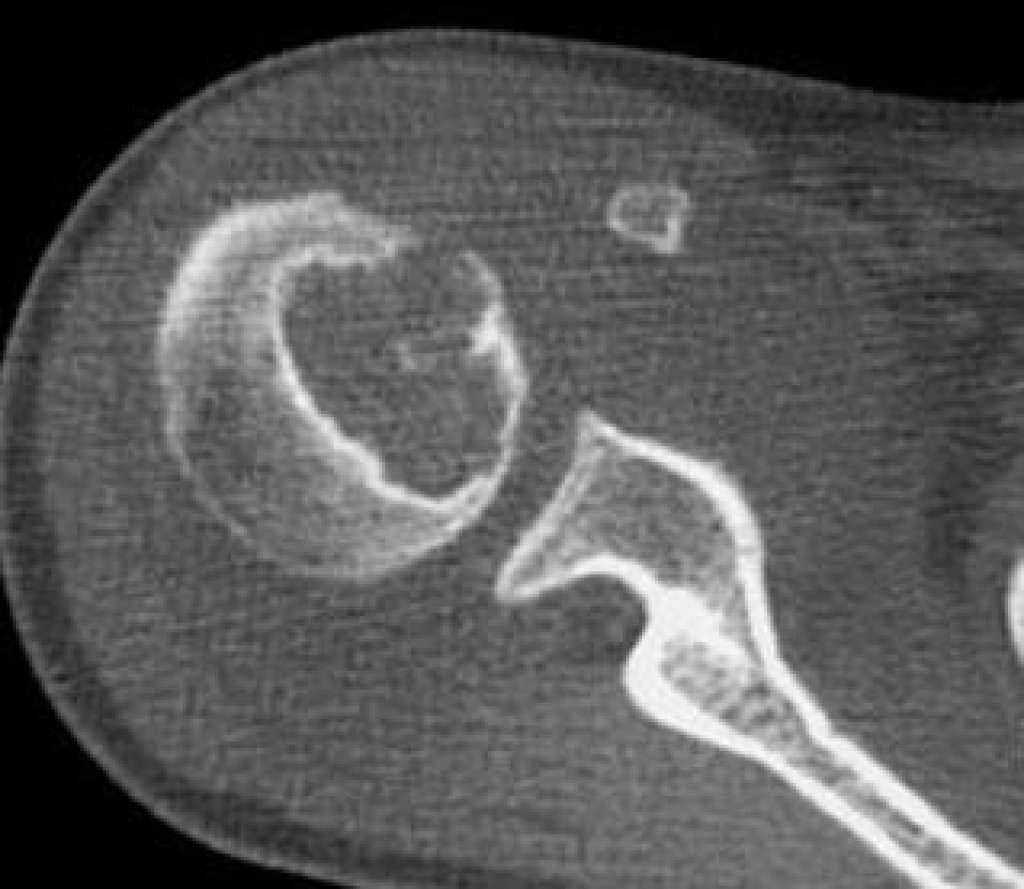

- Комп’ютерна томографія (КТ) відіграє ключову роль у точнішій діагностиці. КТ дозволяє оцінити кісткову деструкцію, дрібні кальцифікати та поширення пухлини як всередині, так і поза кісткою. Близько 95% випадків хондросаркоми демонструють матриксну кальцифікацію на КТ, тоді як на звичайних рентгенівських знімках цей показник становить лише 70%. На КТ також добре видно кортикальний прорив, який є характерною ознакою злоякісності, що спостерігається майже у 90% випадків хондросарком довгих кісток. Це значно відрізняє їх від доброякісних хондром, де такий прорив є рідкістю.